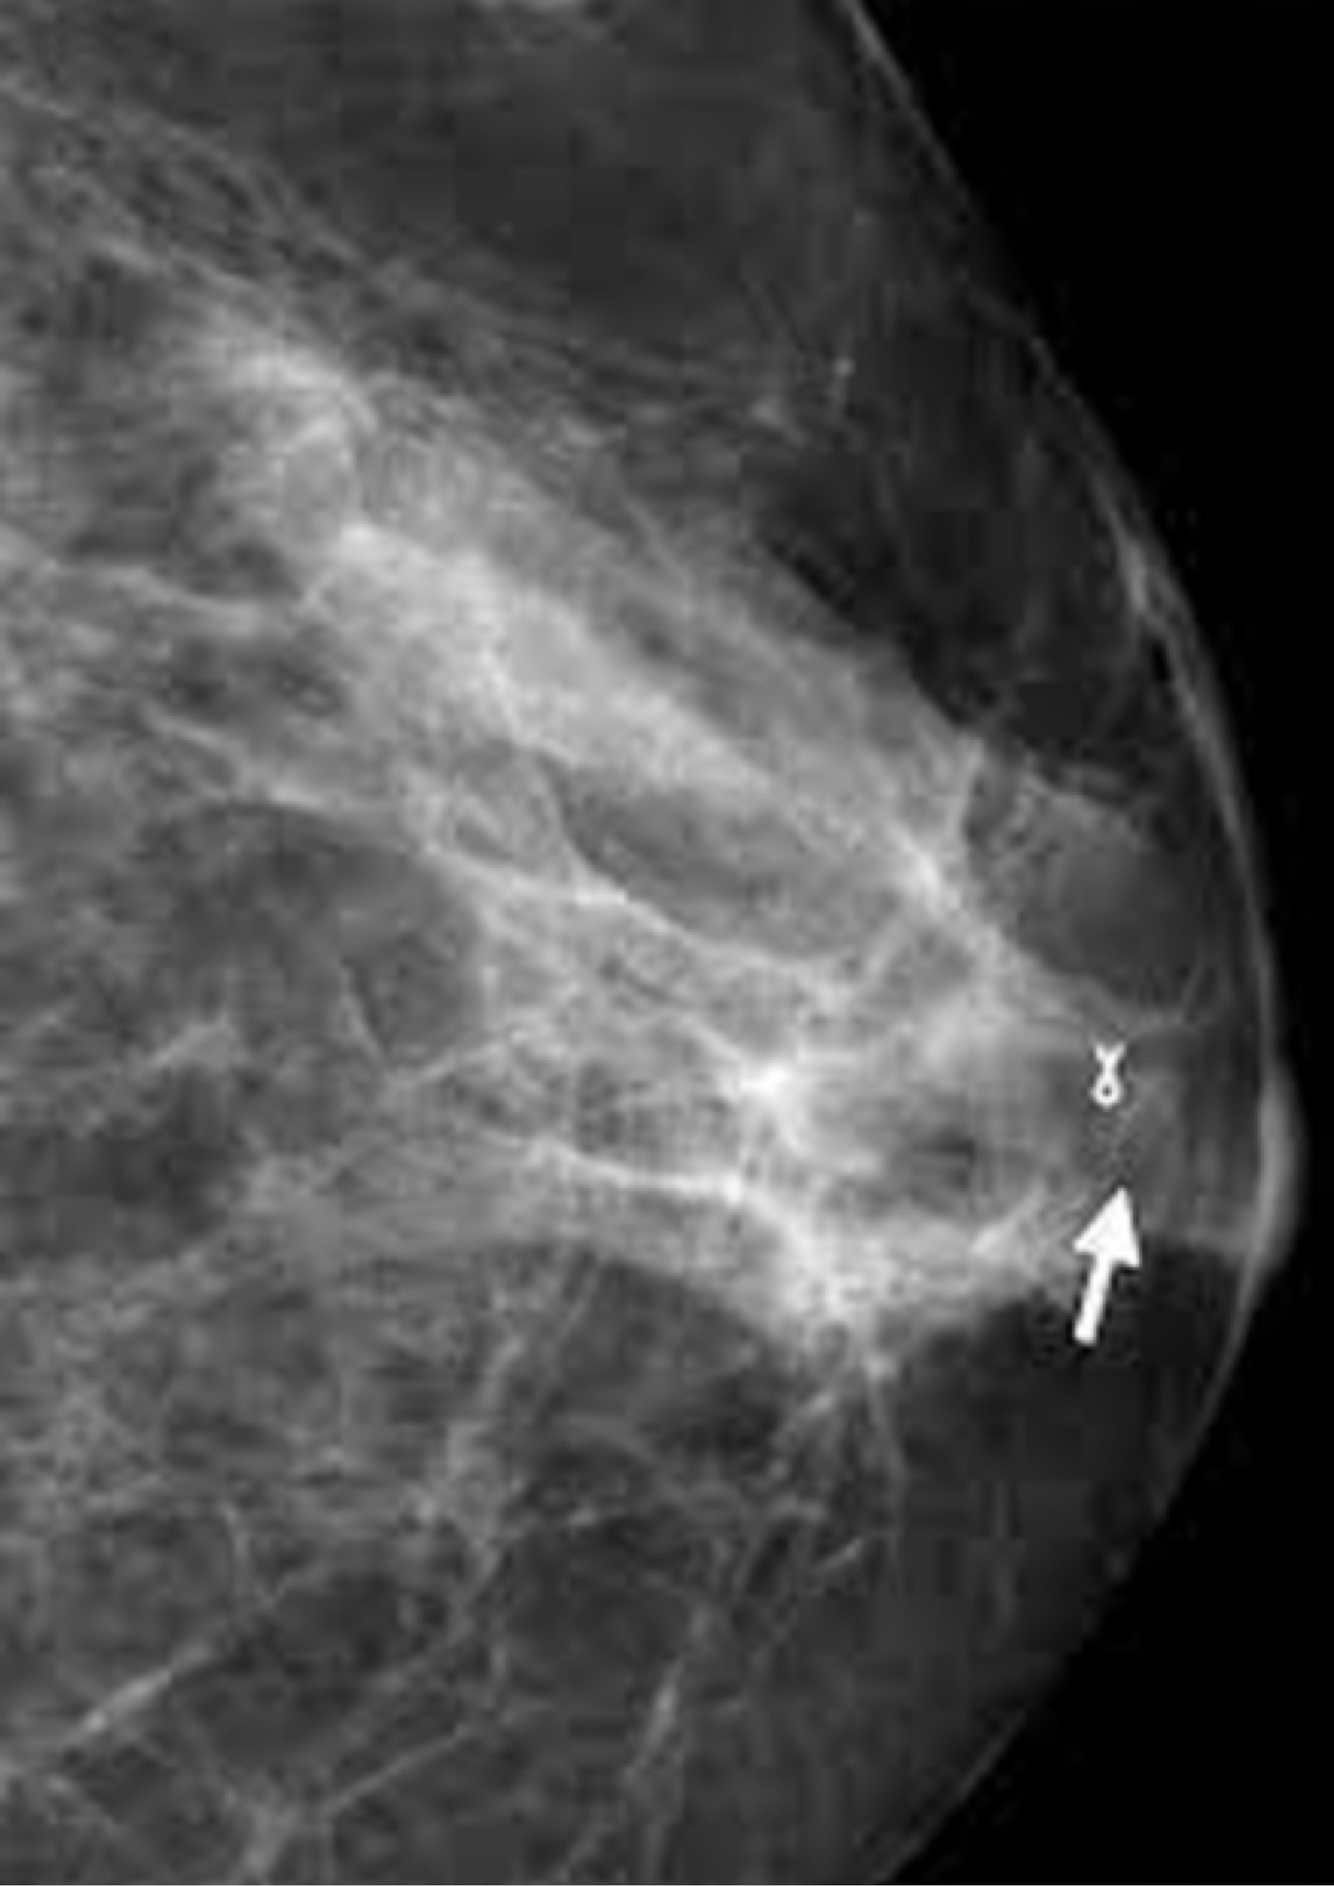

Q

Dx

A

Mastitis